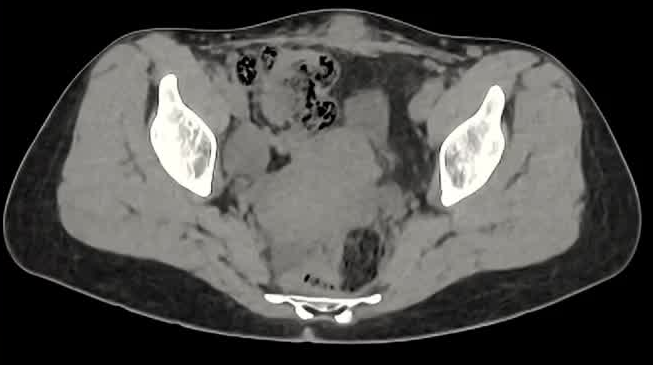

病灶位置:16个疼痛性目标病灶位于脐部(7/16,43.8%)、膈肌(4/16,25.0%)、腹股沟管(3/16,18.8%)和子宫肌肉层(即腺肌症,2/16,12.4%)。

影像引导方式:超声和横断面成像(CT或MRI)结合是最常用的影像引导方式(10/16,62.5%)。

保护措施:几乎所有干预都需要辅助保护措施,其中水分离术(13/16,81.3%)和水分离术与温盐水填充手套的皮肤保护结合(9/16,56.3%)是最常见的保护措施。